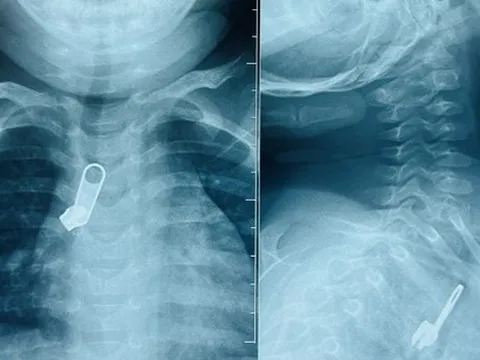

Móc khóa 'đi lạc' vào phế quản bé trai vì sai lầm của người lớn

Phát hiện bé trai 15 tháng tuổi ngậm móc khóa trong miệng, người nhà đã dùng tay móc miệng của trẻ để lấy ra khiến dị vật này bị lọt xuống đường thở khiến bé phải nhập viện.